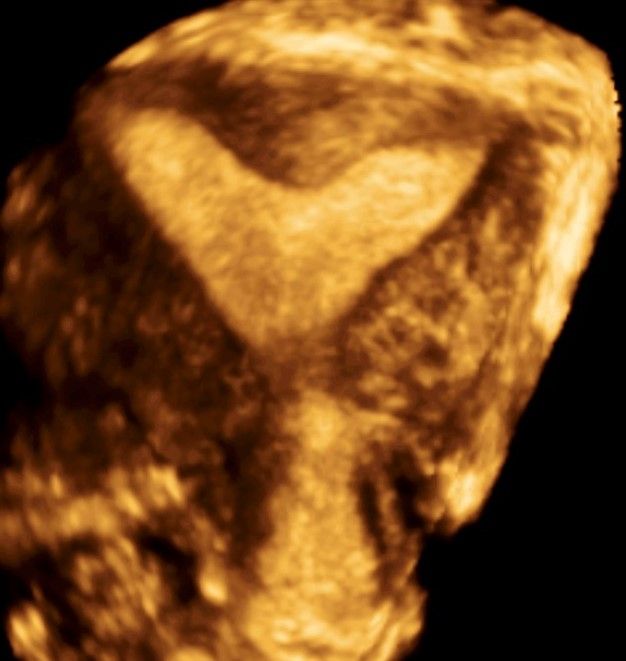

Современные экспертные УЗИ сканеры дают возможность проводить исследования всех органов в 3D. Это позволяет, используя полученный массив данных, получать диагностические сечения в любой плоскости, недоступной для обычного 2D УЗИ. Наиболее интересной является фронтальная. Например, визуализация полости матки. Диагностическая возможность выявления пороков развития превосходит все другие методы (рентгеновские и МРТ). Метод также позволяет уточнить положение ВМК (спирали) в полости матки, расположение миоматозных узлов, расположение плодного яйца на малых сроках, полипов. Сегодня современное экспертное ультразвуковое исследование невозможно без использования 3D УЗИ.